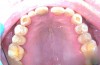

N.P.’s occlusal surfaces exhibited generalized extreme wear and/or erosion, and he complained of dentin hypersensitivity (Figure 2 and Figure 3). A caries risk assessment and diet recall was performed to assess the patient’s diet to determine its impact on the dentin hypersensitivity and caries risk. During the dietary assessment, N.P. reported severe GER problems limited his food selection.

Periodontal assessment revealed (Figure 4 through Figure 9):

• eneralized 4 to 6 mm probing depths on posterior teeth

• Furcation involvement, which included Grade I buccal of the maxillary left first and second molar and ML and Grade II buccal of the maxillary left third molar

• Tooth mobility – Class I maxillary left central incisor

• Bleeding Index: 39.8%

• Plaque Index: 100%

Figure 3  Mandibular Arch

Figure 3